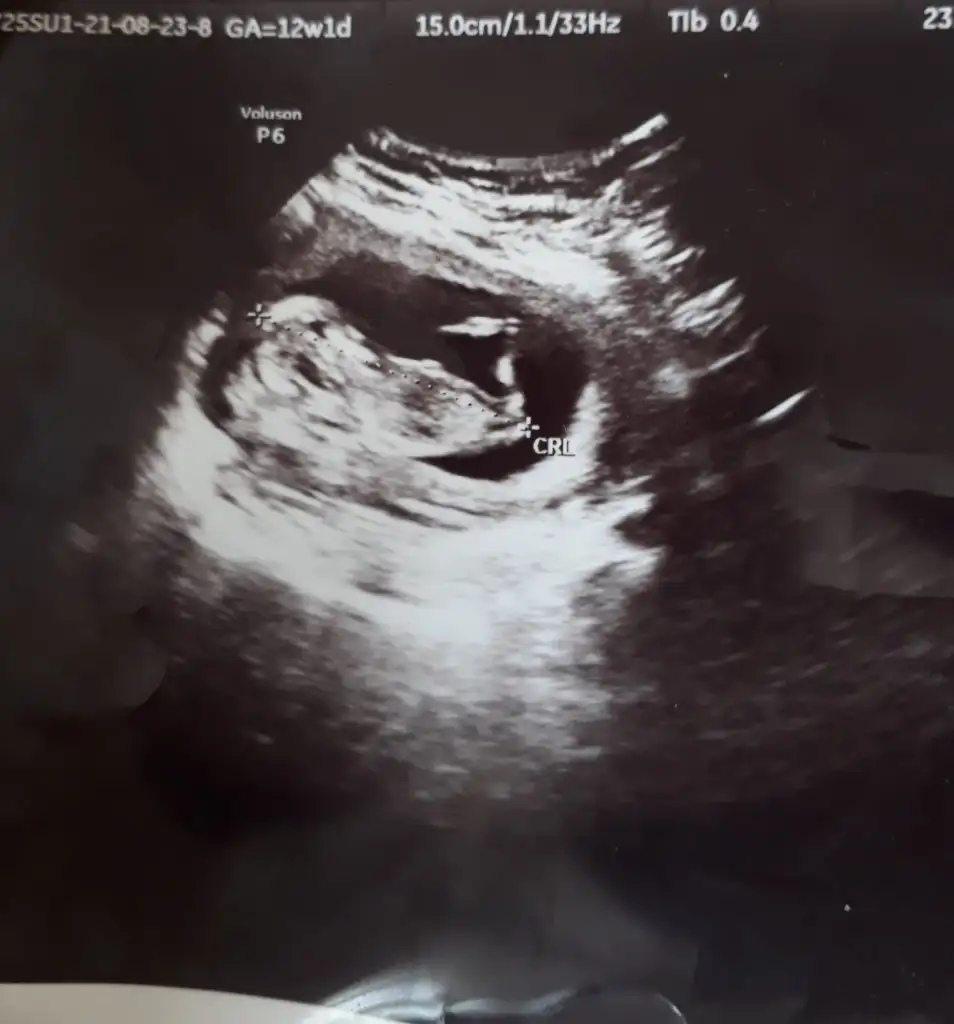

Erkek ve kız için 11 + 12+ yada 13 hafta usg görüntüsü olmalı açıklamalar asagıda yazıyorrabbim herkesin gönlüne göre nasip etsin inşallah .. ecmain

[/B]Eki Görüntüle 473828 gordugunuz gibi ust taraftaki simgedende anlasildigi gibi eger cikinti paralel ise kiz

yok 30°lik bir aciyla yukari dogru bakiyorsa %99 oglunuz olacak demektir simdi bi kac ornek resimler daha koyacagim kiziminkide dahil

Net değil o nedenle yazmadım başka USG varsa paylaşın 10-11-12-13Ikra meyra bana da bir tahmininiz var mıııı yukarıda gözükmedi sanırım tekrar ekliyorum çok merak ediyorum da teşekkür ederim 12+2 günlük burda

11 12 13 haftalar olmalı şimdilik kız yönünde ama yanıltabilir dediğim gibi tekrar USG paylasin